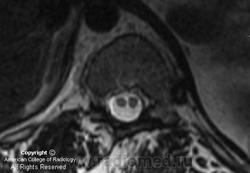

Диастематомиемия.

"НЕЙРОРАДИОЛОГИЯ В СЕТИ". Диастематомиемия шейного отдела.

Диастематомиелия – это врожденная аномалия позвоночного канала и спинного мозга, характеризующееся разделением спинного мозга или конского хвоста на протяжении нескольких позвонков, ассоциированное с костной или фиброзной перегородкой. Предполагается, что наличие данного порока - это результат оставшегося соединения нервной трубки с амниотической полостью или примитивной кишкой. Разделение спинного мозга сопровождается наличием костной, хрящевой или фиброзной перегородки или шпоры, начинающейся от передней стенки позвоночного канала (задняя поверхность тела позвонка) и распространяющейся в позвоночный канал до задних костных структур. Термин диастематомиелия имеет отношение к явлению расщепления спинного мозга на два рукава, а не к перегородке или шпоре и не должен ассоциироваться с такими состояниями как дипломиелия или истинное раздвоение спинного мозга.

Дефиниция. Диастематомиелия (ДМ) - один из вариантов спинальной дизрафии, при котором спинной мозг расщепляется на два рукава перегородкой, расположенной в сагиттальной плоскости. В 1992 г. D. Pang et al. выделили два типа диастематомиелии:

I тип - костная, хрящевая или фиброзная перегородки пересекают позвоночный канал, спинной мозг и его оболочки в сагиттальном направлении;

II тип - разделения позвоночного канала не возникает, а спинной мозг делится фиброзной перегородкой внутри единого дурального мешка на два рукава.

В обоих случаях перегородка имеет переднезаднее направление, но может располагаться не строго в сагиттальной плоскости и не всегда делит спинной мозг на равные части. У многих пациентов имеется выраженная асимметрия развития половин спинного мозга, вплоть до гипоплазии одной из них. Перегородка может располагаться в любом отделе позвоночника. Чаще она встречается в поясничном отделе на уровне L2-L4 сегментов, реже - в грудном, еще реже - в шейном (в последнем случае практически всегда сочетается с синдромом Клипеля – Фейля). Формирование двух и более перегородок в разных отделах позвоночника наблюдается очень редко.

Диастематомиемия (Тип 1)

Диастематомиемия (Тип 2)